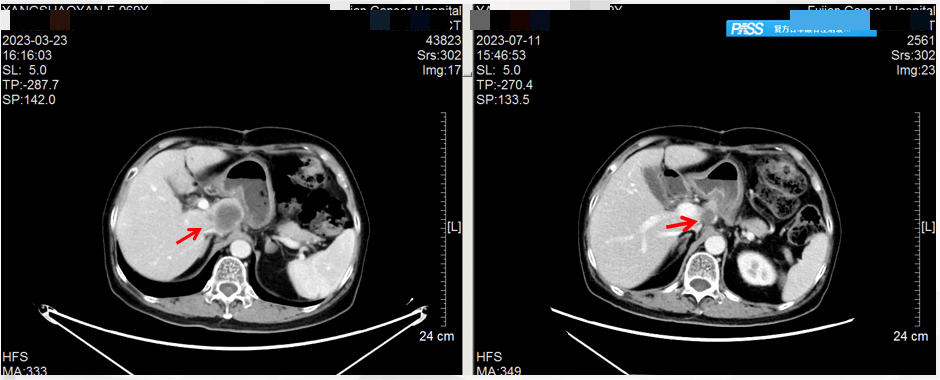

首次复查(2023.7.11):腹部CT:与治疗前(2023.3.23)CT影像对比,提示肝脏多发转移灶均较前明显缩小(图2)。影像学评估:部分缓解(PR)。